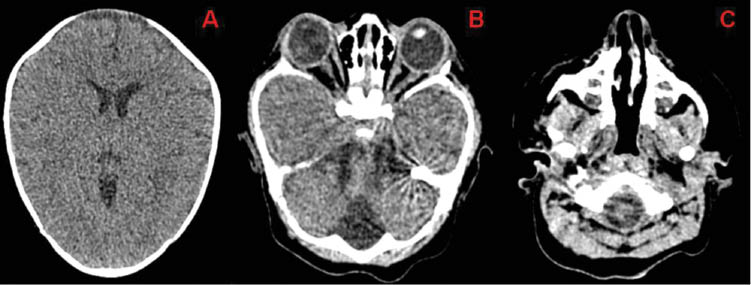

Vertebral and limbs X-ray, audiometry, echocardiography and abdominal echography were normal. In transfontanelar ultrasound we saw asymmetry because of left lateral ventricle enlargement. The scanner images showed cranial asymmetry with early closure of bilateral coronal and metopic sutures, a large bone defect of the sagittal suture, bilateral exotropia and deviated nasal septum (Figure 2). Radiologists made a 3D cranial scanner reconstruction to aid in defining the type of cranyosinotosis (Figure 3).

Cranial scanner images.

(A) Ventricular asymmetry because of a slight enlargement of the left lateral ventricle. (B) Bilateral exotropia. (C) Deviated nasal septum.